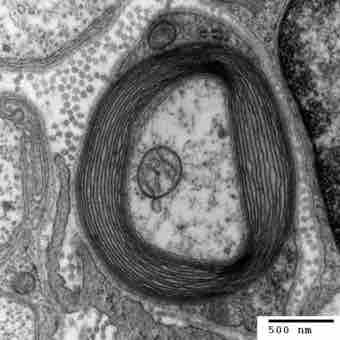

Illustration of the Schwann Cells and the Myelin Sheath

Transmission electron micrograph of a myelinated axon. The myelin layer (concentric) surrounds the axon of a neuron, showing Schwann cells.